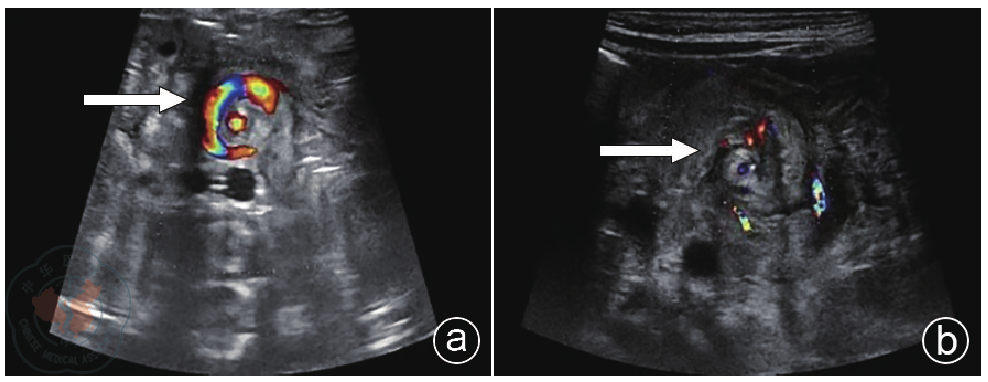

Liling Lu, Xiuzhen Yang, Bin Xu, Lei Zhao, Jingjing Qian, Xiaoying Li, Biao Wang, Jingjing Ye.

Ultrasonic manifestations and diagnostic value of torsion of the pedicle of old ovarian cysts in infants and young children

[J]. Chinese Journal of Medical Ultrasound (Electronic Edition), 2025, 22(08): 748-753.